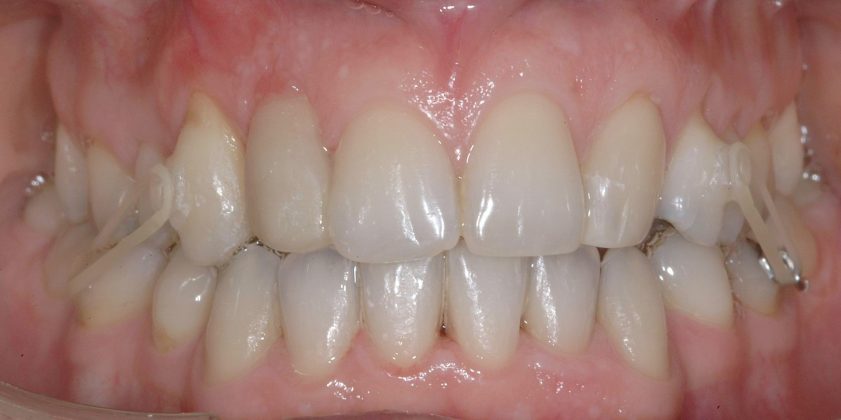

Una paziente di sesso femminile, 38 anni, già trattata ortodonticamente presso altra sede con apparecchiatura fissa a entrambe le arcate in età adolescenziale senza successiva applicazione di alcuna contenzione, si presenta alla nostra attenzione perché insoddisfatta dell’estetica del sorriso; richiede una valutazione per un trattamento ortodontico con apparecchiatura fissa linguale per la presenza di affollamento dentale a entrambe le arcate e difficoltà a mantenere una adeguata igiene orale; si riscontrano agenesia di entrambi gli incisivi laterali superiori (1.2 e 2.2) e del secondo premolare inferiore destro (4.5). Presentiamo la risoluzione del caso mediante trattamento ortodontico estrattivo a entrambe le arcate, eseguito con apparecchiatura linguale invisibile 2D e meccanica asimmetrica e seguito a medio termine da riabilitazione implanto-protesica e contenzione fissa.

Per formulare corretta diagnosi e piano di cura, lo studio del caso ha previsto la raccolta di documentazione completa standard, ovvero fotografie del viso e intraorali (Figure 1a-e), radiografia panoramica e teleradiografia del cranio in proiezione laterale (Figure 2a-b) per la relativa analisi cefalometrica e modelli di studio.

La valutazione clinica e gli esami effettuati confermano la presenza di agenesia degli incisivi laterali superiori (1.2 e 2.2) e del secondo premolare inferiore destro (4.5).

L’analisi ortodontica e la valutazione parodontale, con particolare riferimento alla posizione della radice del canino superiore destro (1.3), distoinclinata e trasposta alla radice del primo premolare (1.4) come evidente dalla radiografia panoramica e dalle immagini intraorali, ci hanno guidati nella programmazione di un trattamento estrattivo asimmetrico a entrambe le arcate.